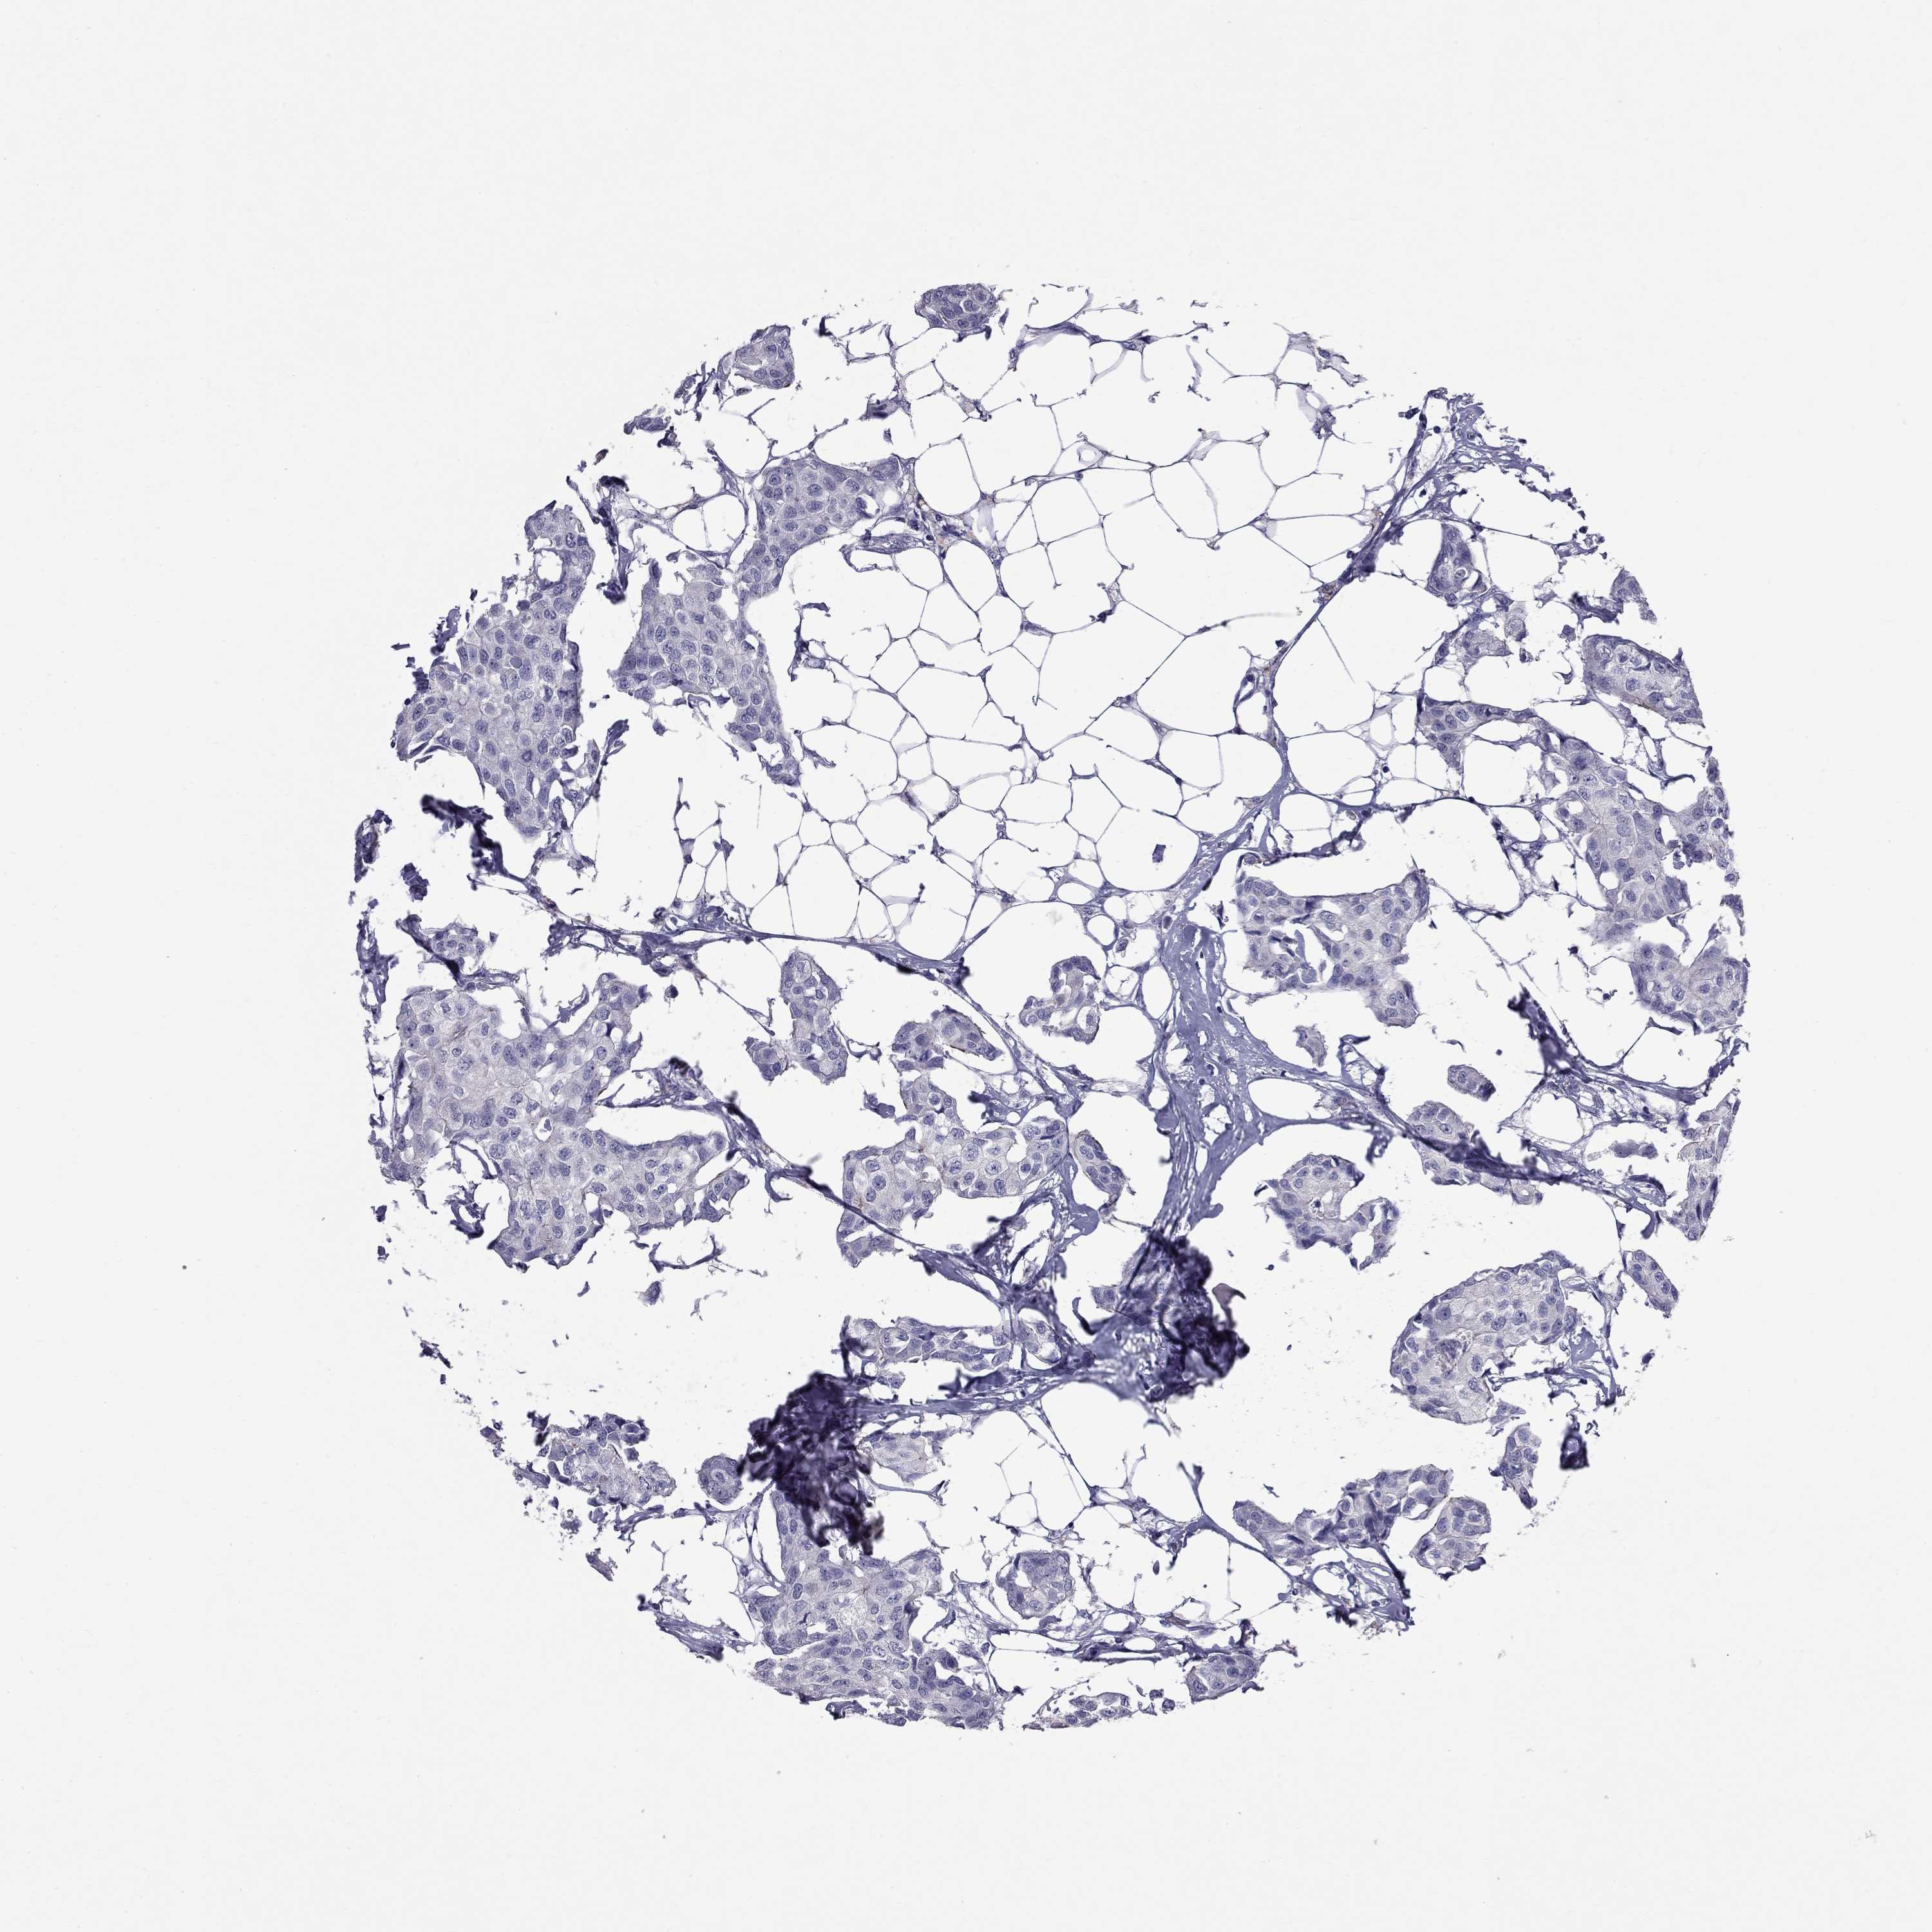

CANCER BREAST CANCER Show tissue menu

BRCA TCGA BRCA VALIDATION PROTEIN EXPRESSION